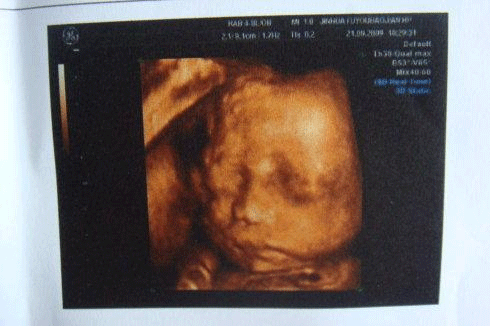

30周4天的小排畸检查

小排畸检查在30周左右